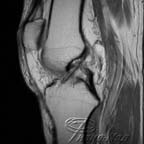

Рентгенограммы терпят неудачу при диагностировании заболеваний мягких тканей, хрящей колена, локтя и других суставов. На рентгенограммах хорошо видны кости, а вот мягкие ткани и хрящи рентген не видит. МРТ суставов обеспечивает детализированные изображения всех структур сустава, включая кости, хрящи, сухожилия, связки, мышцы и даже кровеносные сосуды.

Детализированные изображения суставов предоставляют 3D визуализацию и позволяет врачам лучше определять наличие определенных заболеваний, которые не могут быть адекватно диагностированы другими методами, такими как рентген, ультразвук или компьютерная томография (КТ).

Результаты МРТ обследований очень точны при диагностировании разрывов менисковой и крестовидной связки . Это - самый адекватный инструмент обследования перед терапевтической артроскопией. МРТ также дает хорошие результаты в обнаружении лучевых разрывов среднего мениска у пожилых пациентов. У этой группы пациентов часто присутствует остеоартрит, который может маскировать симптомы разрывов.

Магнитно резонансная томография в состоянии обнаружить большинство внутренних расстройств колена очень эффективно. Одновременно МРТ, также правильно идентифицирует и отсутствие внутренних патологий коленных суставов. У МРТ точность диагностики среднего мениска превышает 91.4 % .

3D томография позволяет проводить идентификацию всех сопутствующих внутрисуставных патологий суставов в течение нескольких минут с точностью, сопоставимой с артроскопией.